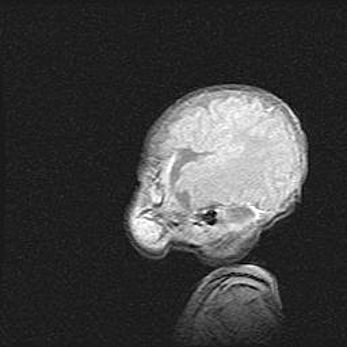

Неполная лизэнцефалия (пахигирия). Открытая гидроцефалия.

Возраст: 17 дней

Вес: 3110 г

Пол: мужской

Окружность головы: 33,5 см

Срок гестации: 35-36 недель

Лизэнцефалия—недоразвитие корковой пластинки и мозговых извилин в результате нарушения миграции нейронов коры. Поверхность мозговых полушарий гладкая. Микроскопически выявляется отсутствие нормальных слоев коры и скопление групп нейронов в подкорковом белом веществе.

Пахигирия—уменьшение числа вторичных извилин. В пораженном полушарии нервные клетки образуют толстый недифференцированный слой с неправильно расположенными нервными волокнами и группами гетеротопных клеток. Нервные клетки незрелые. Белое вещество истончено. При этом нередко аномально развит корково-спинномозговой путь.